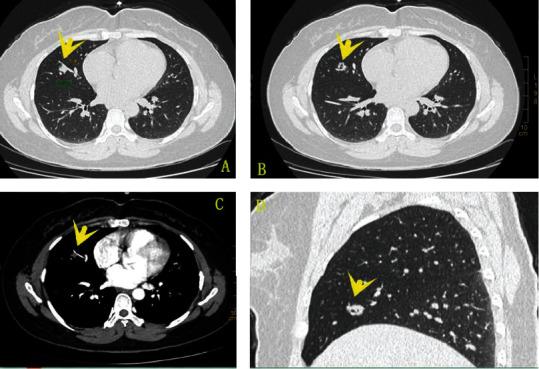

Bronchiolar adenoma (BA) is a rare lung tumor that has recently been clearly named, including the previous ciliated muconodular papillary tumor (CMPT) and the so-called nonclassical CMPT. The most prominent histological feature of BA is a double-layer cell structure composed of a continuous basal cell layer and a luminal cell layer. BA lined purely by mucinous luminal cells is very rare, and only one case has been reported in the English literature. This type of BA can easily be misdiagnosed as early mucinous adenocarcinoma. This article analyzes the clinicopathological characteristics of a newly discovered case of BA lined purely by mucinous luminal cells and fully integrated with the literatures.

细支气管腺瘤(BA)是一种罕见的肺肿瘤,最近才被明确命名,包括之前的纤毛黏液结节状乳头状瘤(CMPT)和所谓的非典型CMPT。BA最显著的组织学特征是由连续的基底细胞层和管腔细胞层组成的双层细胞结构。纯由黏液性管腔细胞内衬的BA非常罕见,英文文献中仅报道过1例。这种类型的BA很容易被误诊为早期黏液腺癌。本文分析了1例新发现的纯由黏液性管腔细胞内衬的BA的临床病理特征,并结合文献进行全面分析。